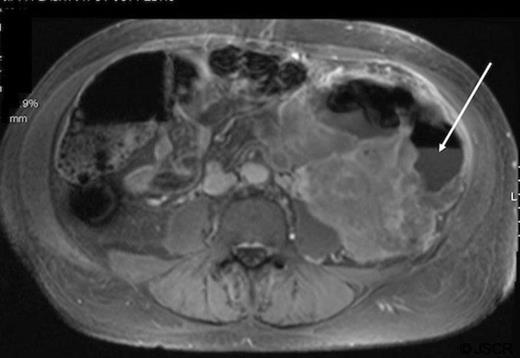

Patient A is a 67 year old female with a history of pelvic leiomyosarcoma and total abdominal hysterectomy with bilateral salpingo-oopherectomy who presented with abdominal discomfort, early satiety and weight loss. On physical exam she was noted to have a large, firm abdominal mass. Admission labs revealed a marked leukocytosis (WBC=45 700) and blood cultures positive for E. coli. CT of the abdomen and pelvis revealed a mass occupying the pelvis and majority of the abdomen with air pockets, questionable portal venous gas and mild left hydronephrosis (Figure 1).

Abdominal and pelvic CT of patient A demonstrating a large mass with air pockets (arrow).